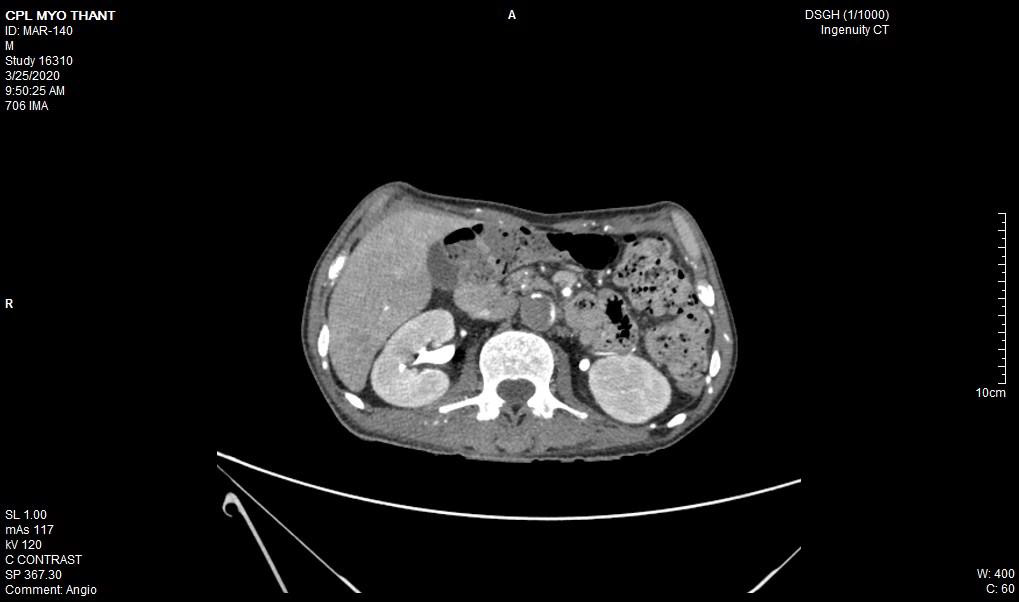

As his left femoral artery pulsation became weak and thus, CT Aortogram was done (4 weeks after symptom onset of right femoral artery occlusion). It revealed extensive thrombosis with complete obstruction of abdominal aorta starting below the level of celiac trunk- both renal arteries and both iliac arteries. The calcifications of the arterial wall at aortic arch, thoracic and abdominal aorta and both iliac vessels were seen too. (Figures 5-11) Thus, he had severe atherosclerosis due to hypertension and heavy smoking. Occlusion of both renal arteries explained his high blood pressure. The cholesterol and uric acid level were normal. He was treated with atorvastatin, aspirin, clopidogrel, antihypertensives, wound care, physiotherapy, intensive nursing care nutritional support and antibiotics.

This patient had on going ischaemia as the wound was not healing well and diminished left femoral pulsation. And it was a clinical clue to arterial obstruction at higher level – above femoral artery. It was proved by CT angiogram.

Regarding the aetiology of arterial occlusion in this 43-year-old patient, relatively young age, severe atherosclerosis was the main culprit as there were extensive atheromatous plaque in wall of the whole aorta and it was aggravated by smoking and hypertension. It was the main reason for reporting this case. Moreover, It was not due to COVID-19 infection because it was excluded initially though there were few case reports having deep vein thrombosis, pulmonary embolism and arterial thrombosis due to COVID-19 infection [11-13].

In essential thrombocythemia, recurrent thrombosis of same artery was seen in some cases [7,8]. Moreover, thrombosis at multiple site was reported too [14,2]. It commonly causes obstruction of small vessels and rarely to median and large arteries. Nevertheless, there were reports on essential thrombocythemia producing thrombosis of aorta [15-17]. In this case, combination of hypertension, smoking, severe atherosclerosis and essential thrombocythemia gave rise to extensive thrombosis of aorta; the rare variety of this case.